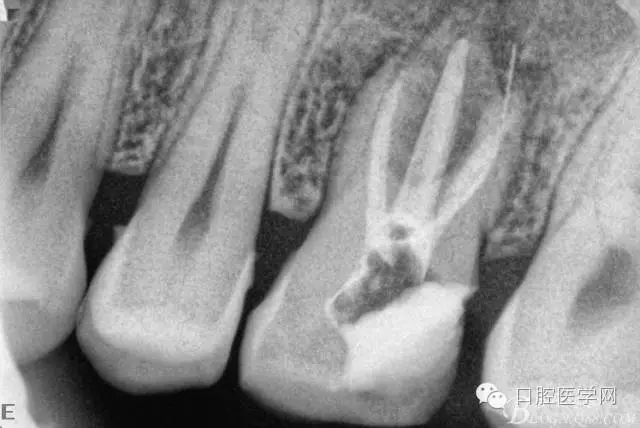

根充后三個(gè)月。

根充后四個(gè)月。根尖炎性陰影明顯減小,唯獨(dú)遺憾的是遠(yuǎn)頰根一斷針,不知后續(xù)如何,日后再行根尖手術(shù)吧。